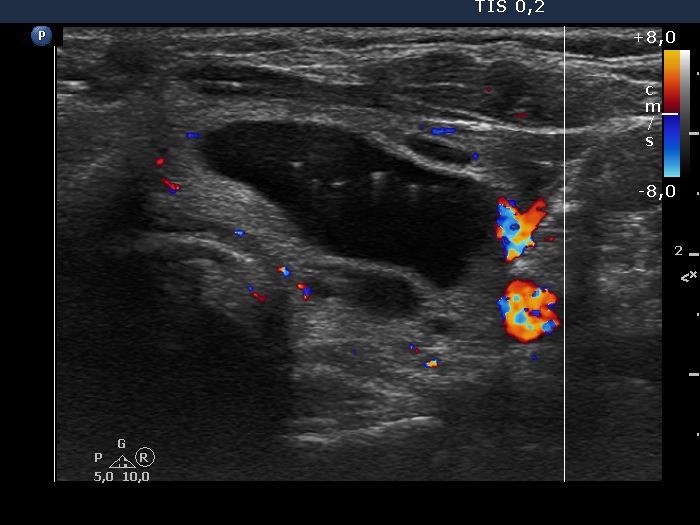

The composition of the nodule - case 1297 (ultrasonographic picture 10)

Left lobe, transverse scan, color Doppler mode - after aspirating of 7.5 mL brown fluid. The lesion presents signs of perinodular blood flow.